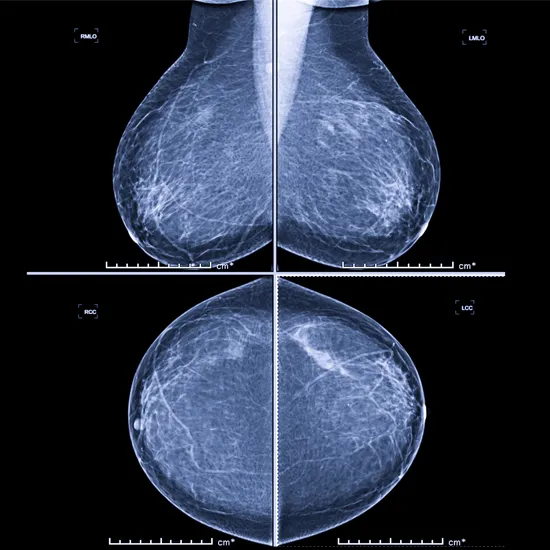

Mammography is the method of examining the breasts of a person using low-energy X-rays for the purposes of diagnosis and screening.

Mammography's primary purpose is to identify breast cancer in its earliest stages, often by locating breast abnormalities that manifest as unusual lumps or microcalcifications.

Mammography is an X-ray diagnostic imaging method which is used to evaluate the breast for disease, lumps and cancer.It serves as a screening and diagnostic tool. Its golden tool in early diagnosis of breast cancer.

To visualise and assess breast tissue and surrounding lymph nodes for cancer, inflammation, abscess, tumour, and cysts.

A mammogram is a type of breast X-ray that physicians use to check for breast cancer and identify any anomalies in the breast tissue. Mammograms are thought to be a helpful test for early detection of breast cancer, even before symptoms appear. Sometimes they take up to three years to manifest or become noticeable.

Mammography examination also known as mammogram. It uses a very low dose of X-rays to examine the breast.